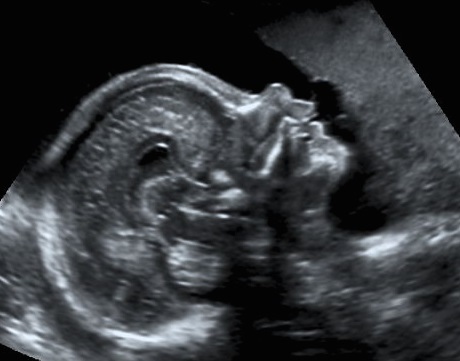

Detaillierte Organdiagnostik im zweiten Trimenon

(19. bis 22. Schwangerschaftswoche)

Beim detaillierten Organultraschall können wir differenziert das Wachstum des Fetus, seine Organe und deren Funktion beurteilen. Speziell untersucht wird das kindliche Herz (siehe hierzu auch „fetale Echokardiographie“). Die Diagnostik einzelner Organfehlbildungen, aber auch teils komplexer, eventuell genetisch bedingter Syndrome ist möglich. Neben Entwicklungsstörungen können Fehlbildungen festgestellt werden, die zum einen den Verdacht auf Chromosomenanomalien, aber auch auf angeborene Infektionen wie Röteln, Toxoplasmose, Zytomegalie, Varizellen und Ringelröteln aufkommen lassen. Durch weitere diagnostische invasive Maßnahmen (z.B. Fruchtwasserpunktion) kann dann eine differenzierte Abklärung erfolgen.